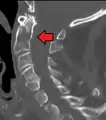

Type 3 odontoid fracture